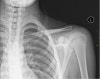

근골격계 통증 질환에 있어 X-ray가 가장 필요한 경우는 외상입니다.

외상으로 인한 골절을 감별하거나 구조적인 문제를 찾고자 할 때는 X-ray는 분명 유용한 도구입니다.

하지만 과사용으로 인한 통증, 경미한 타박상, 연조직 손상의 진단에는 대부분의 경우 X-ray가 필요하지 않습니다.